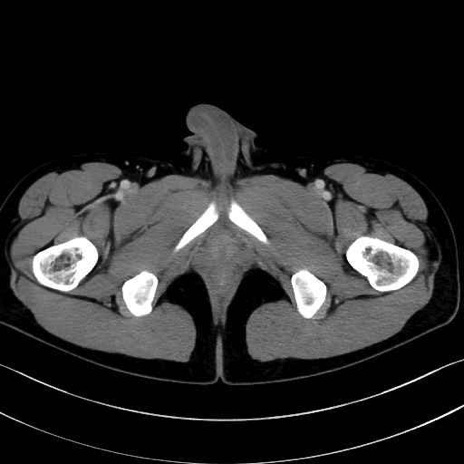

2. 腸腰筋群と骨盤底筋

肛門挙筋 (Levator ani)